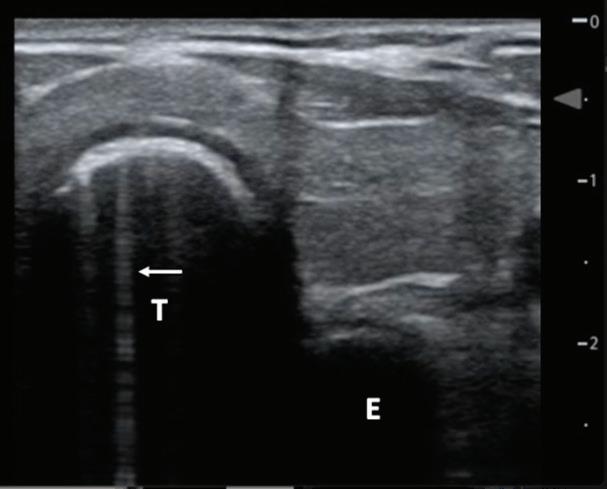

September/October 2023 Common Sense by American Academy of Emergency Medicine - Issuu